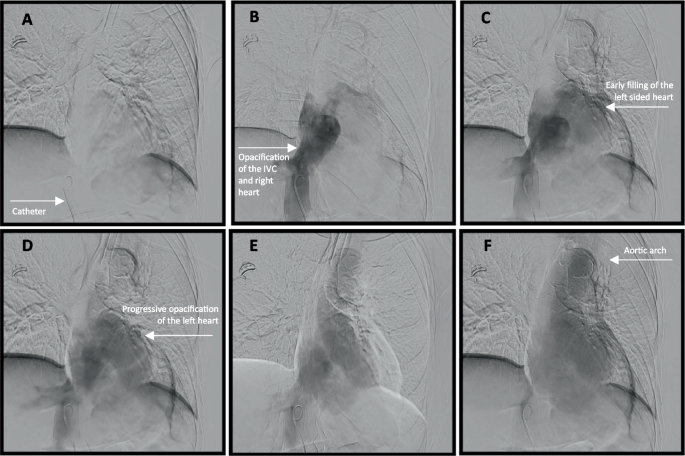

图2

A 导管穿过下腔静脉并到达心房-腔静脉交界处。B 注入造影剂。CE 主动脉逐渐显影